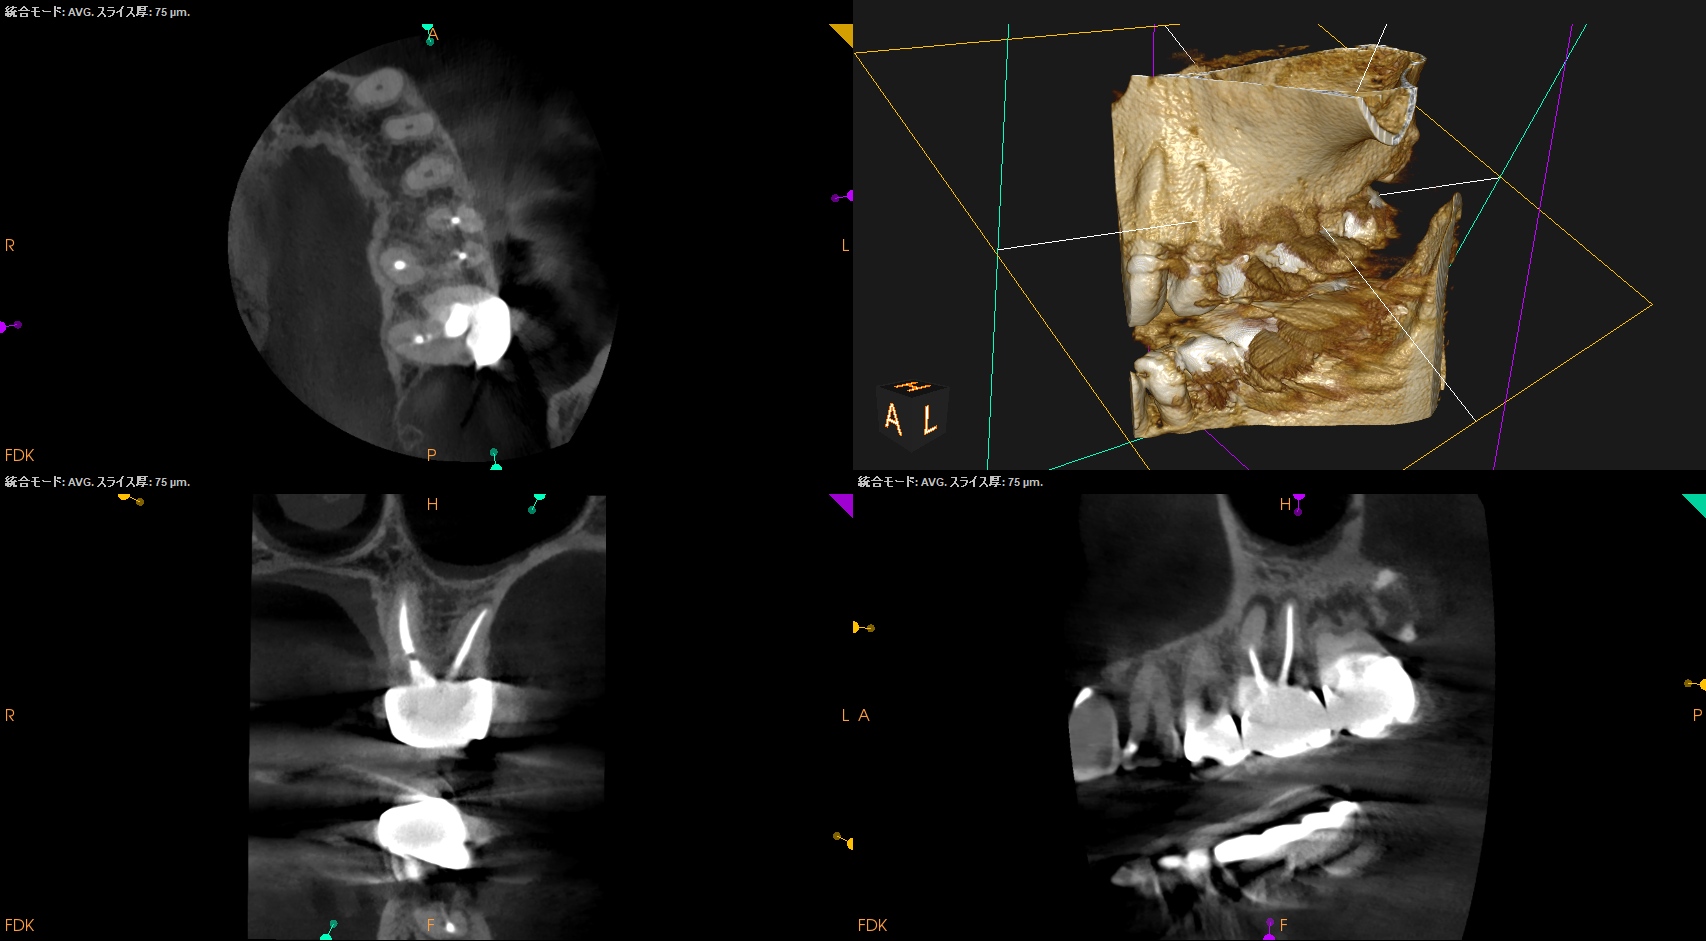

#14 MB Apicoectomy(2025.3.31)

ペリオプローブを使用し、MBのApexを類推した。

OsteotomyしApexから3mmで切断した。

その後メチレンブルーで染色し、CBCTの絵と相似になっていることを確かめて逆根管形成した。

Lid techniqueで逆根管充填した。

術後にPA, CBCTを撮影した。

最後に縫合して終了した。